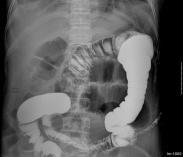

KUB平片:顯示腎實質內呈簇狀,放射狀或多數性粟粒狀排列的鈣化和結石。

IVU:顯示腎盂腎盞正?;蚰I盞增寬,杯口擴大突出,于其外側見到造影劑在擴大的腎小管內呈扇形、花瓣狀、葡萄串狀和鑲嵌狀陰影,囊腔間不相連。由于結石密度不均勻,邊緣不整齊,環繞于腎盂腎盞周圍的多數囊腔似菜花狀。腎功能不佳者可行大劑量靜脈點滴尿路造影,能更清晰地顯示上述特征。逆行腎盂造影對診斷的作用不大。